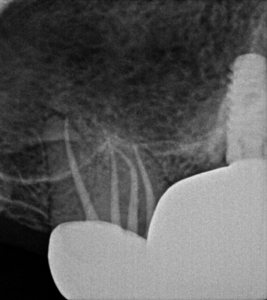

Maxillary Second Molar Root Canal

The following case was an interesting and fairly difficult root canal procedure from a week ago. I normally see maybe one or two of these